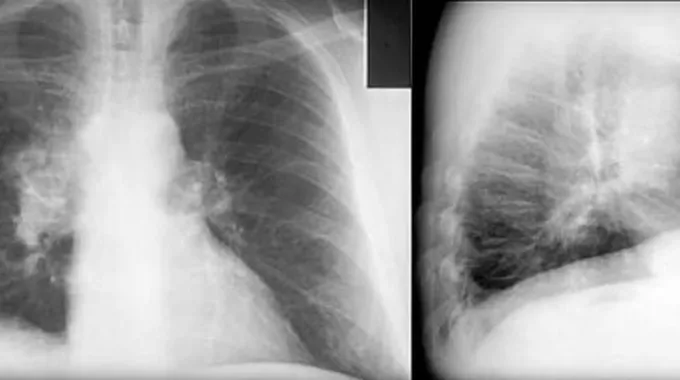

أعراض سرطان الرئة

تختلف الأعراض الناتجة عن الإصابة بسرطان الرئة بحسب مكان السرطان وكيفية انتشار الورم، وقد لا يسبب هذا السرطان أيّ ألم أو أعراض في بعض الحالات، وفي حالات أخرى، فإنّه قد يسبب بعض الأعراض، ومنها:[8]

- السعال الشديد، أو زيادة حدة السعال المزمن الذي يعاني منه المريض.

- خروج دم مع البلغم.

- التهاب القصبات الهوائية، والإصابة بعدوى الجهاز التفسي بشكلٍ متكرر.

- الشعور باختناق وضيق في التنفس.

- الشعور بآلام في الصدر.

- حدوث بحّة في الصوت.

- الشعور بآلام في الكتف، وذلك عند وصول الورم إلى الأعصاب.

- صعوبة البلع.

- فقدان الوزن بشكلٍ غير مبرر.